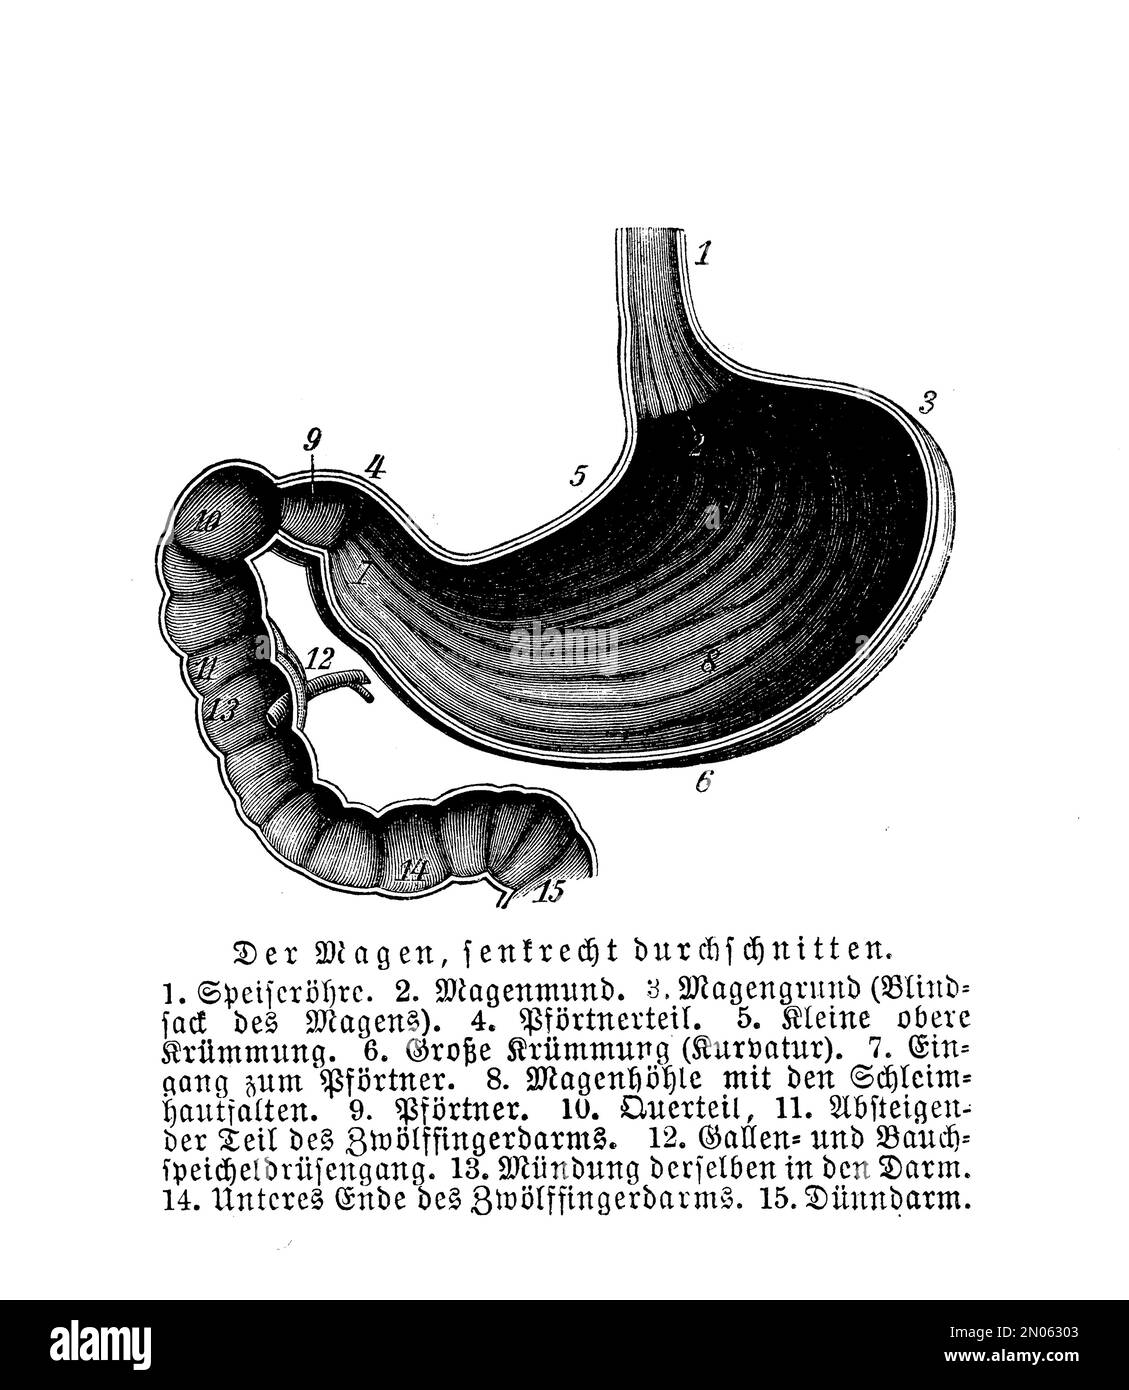

Vintage illustration of anatomy, human stomach with German descriptions Stock Photohttps://www.alamy.com/image-license-details/?v=1https://www.alamy.com/vintage-illustration-of-anatomy-human-stomach-with-german-descriptions-image516445107.html

Vintage illustration of anatomy, human stomach with German descriptions Stock Photohttps://www.alamy.com/image-license-details/?v=1https://www.alamy.com/vintage-illustration-of-anatomy-human-stomach-with-german-descriptions-image516445107.htmlRM2N06303–Vintage illustration of anatomy, human stomach with German descriptions